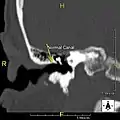

Exostosis in ear canal